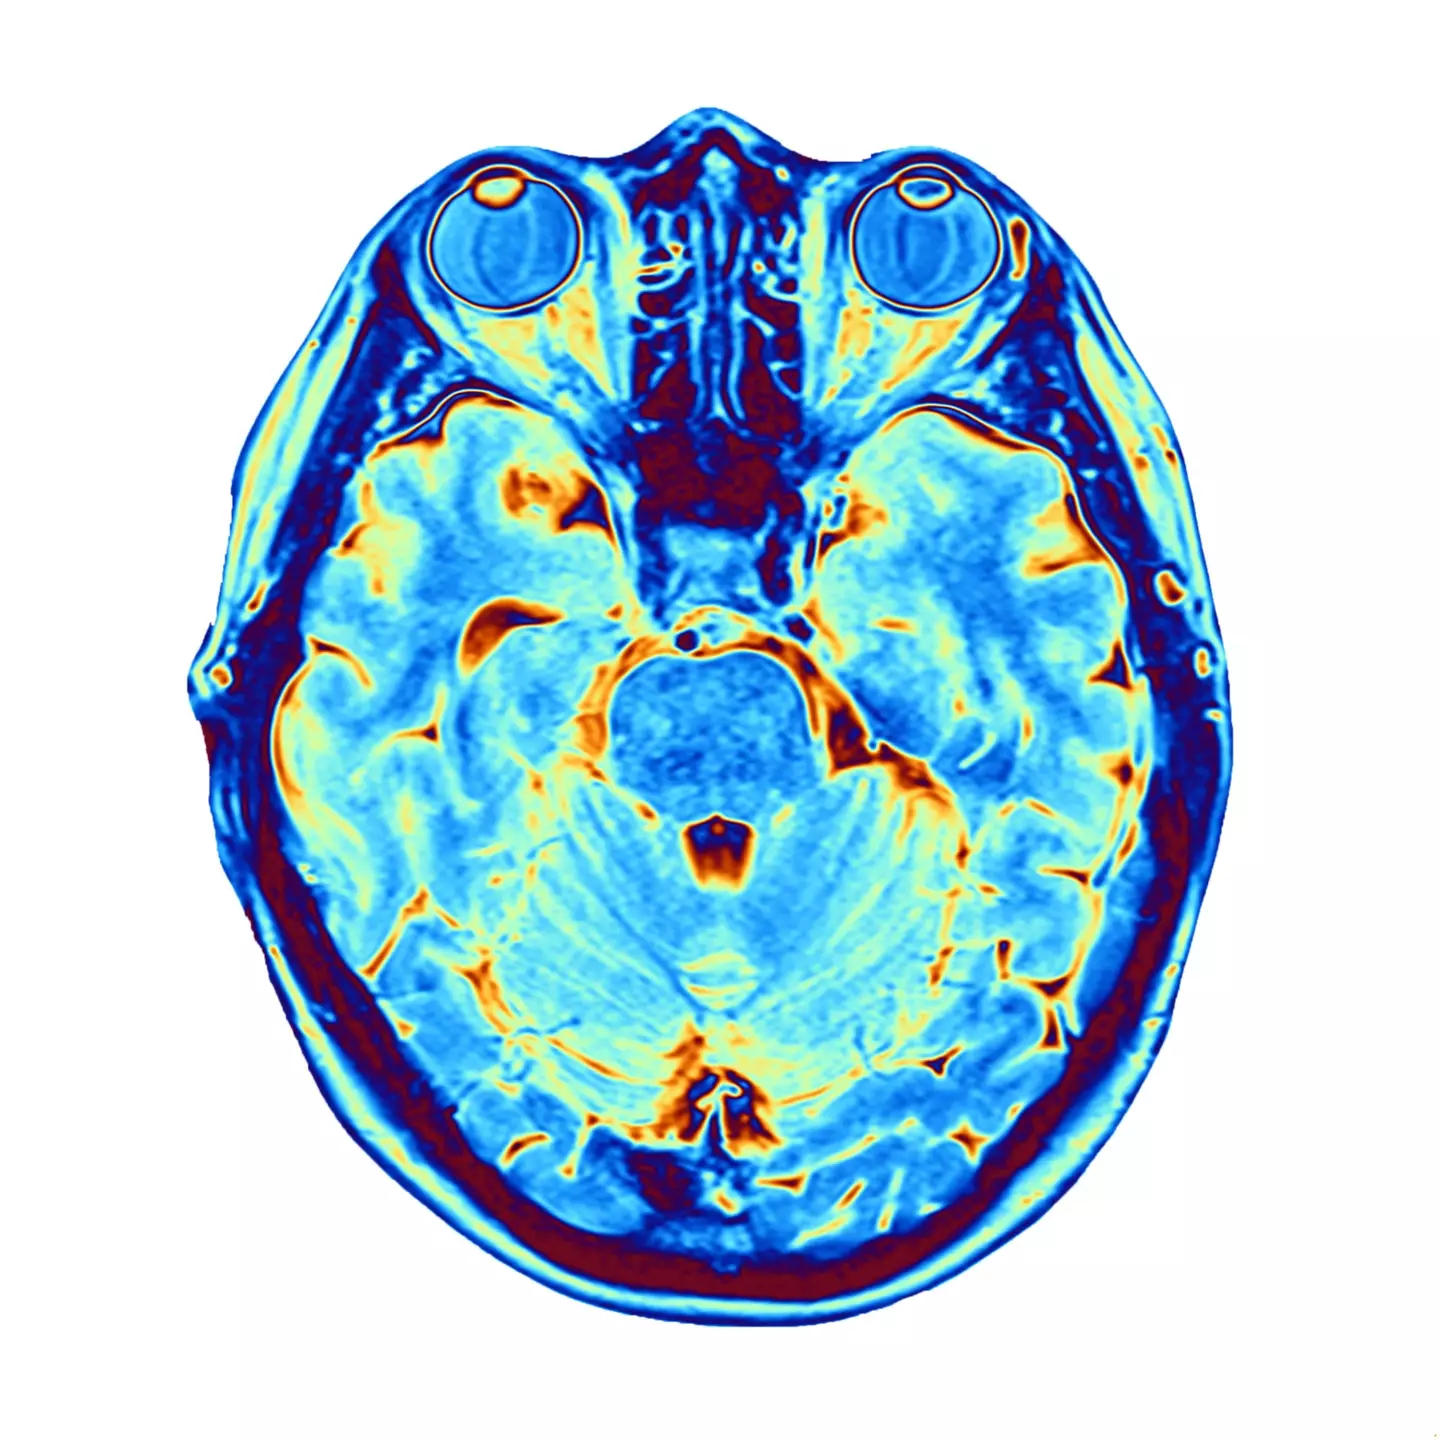

The data was discovered when a team of scientists measured the brainwaves of an 87-year-old man who had developed epilepsy.

However, the patient sadly suffered a fatal heart attack while the team were conducting a neurological reading, which revealed an unexpected insight into what can happen when a person dies.

The recording - which is the first ever recording of a dying brain - indicated that in the 30 seconds before and after death, brainwaves followed patterns similar to dreaming or recalling memories.

Scientists think the findings could suggest a 'flashback' before the end of life.

Dr Ajmal Zemmar, co-author of the study - which was published in Frontiers in Aging Neuroscience - told the BBC: "This was actually totally by chance, we did not plan to do this experiment or record these signals," he said.

Dr Zemmar added that the activity continued for 30 seconds after the patient's heart stopped beating.

"This could possibly be a last recall of memories that we've experienced in life, and they replay through our brain in the last seconds before we die," he said.